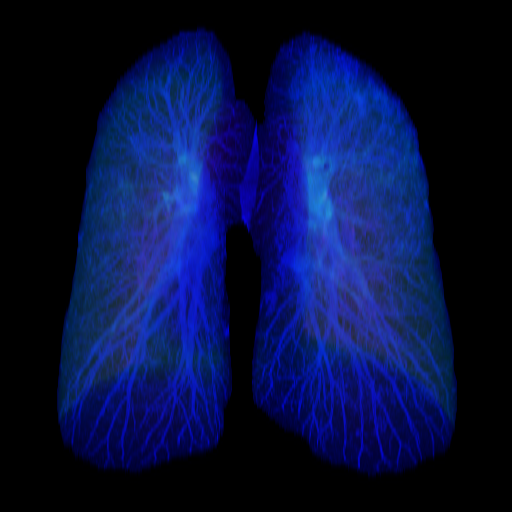

- 1.2 Examples of homogeneity in medical imaging modalities illustrating the similarity of the underlying subject (PET, CT, and MRI).

- (b) CT scan of the brain99footnotemark: 9

Thirdly, while seeming counter to the second point, while in a broad sense medical images are heterogeneous due to the very different imaging techniques and separation based on medical specializations (head scans vs foot scans), within a given data type, there is very high visual similarity. For example, all chest X-rays will look very similar due to standardized acquisition methods and tools, but also in large part, due to the high homogeneity of the human biology, see figure 1.2. For the chest scan example, most human bones and organs will have almost identical structures, similar sizes, and composition. Furthermore, the way these scans are collected is standardized, so the patients will all be positioned at the same angle and distance from the imaging machines. This is true even for data samples that have completely different labels, as the characteristics that indicate one diagnosis or another are often identified by very small, granular differences, which are visually very small in absolute terms. This poses a challenge to researchers in the sense that they can’t directly adapt many of the more recent and best-performing classes of Self-Supervised methods, such as contrastive learning. This has allowed us to develop methods that are tailored specifically for medical images.